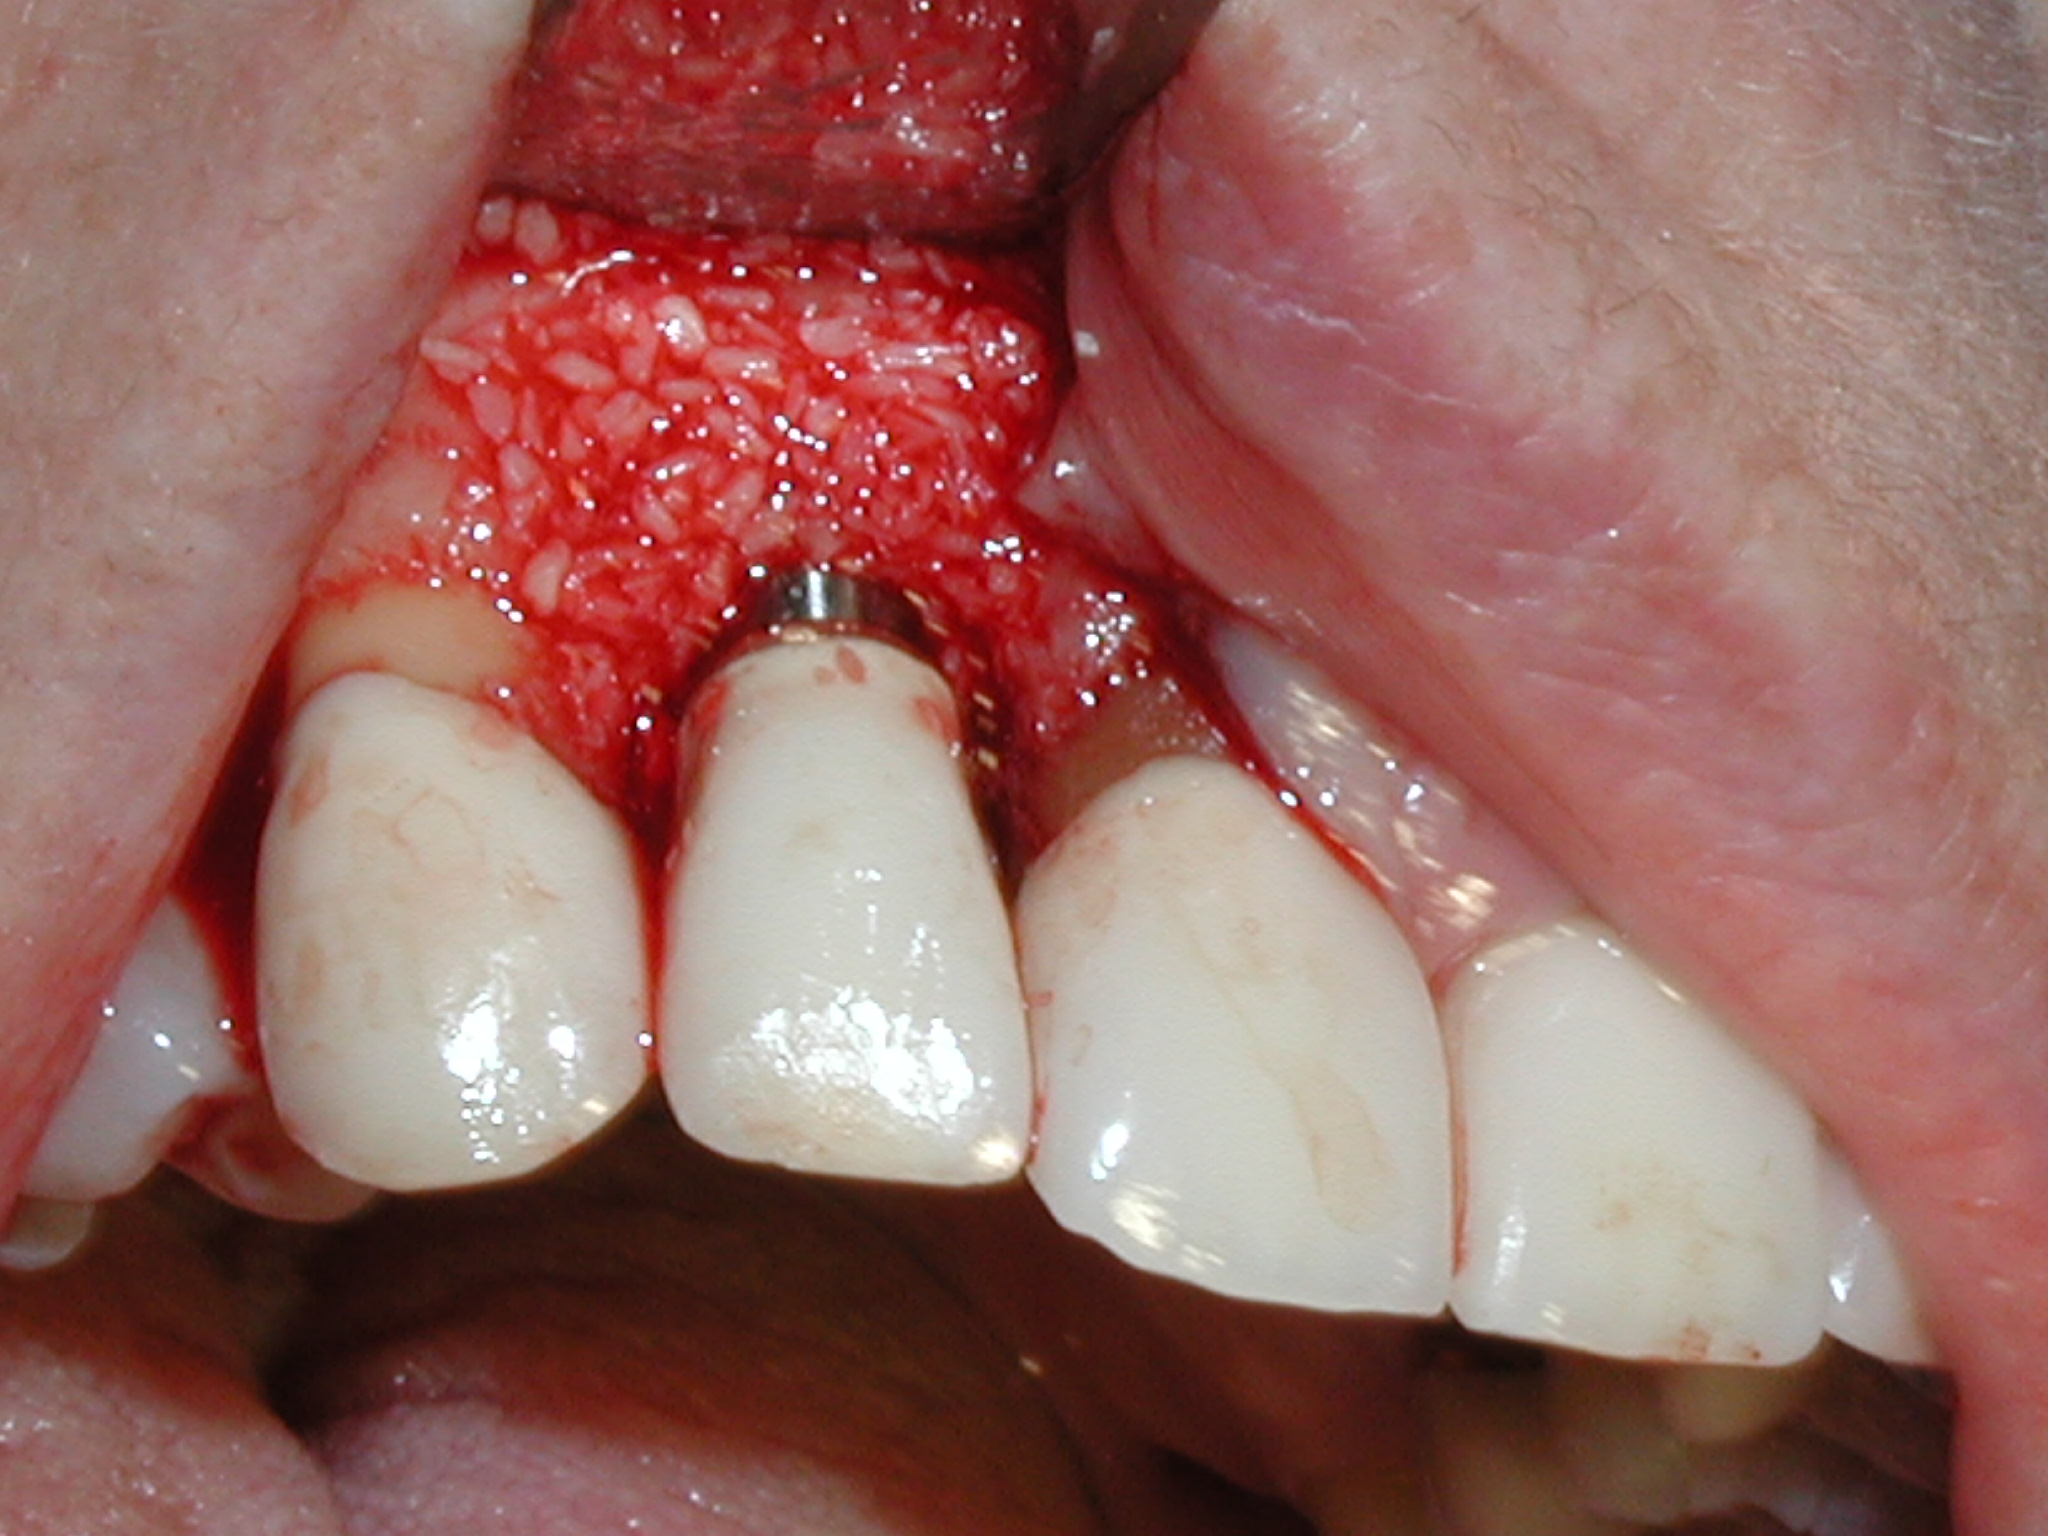

A guided bone regeneration (GBR) approach involving implant surface detoxification (Figure 2), placement of a bone graft combined with a barrier membrane (Figure 3 and Figure 4), and use of a systemic antibiotic has demonstrated the most predictable improvement in peri-implant parameters after destruction of supporting bone. GBR procedures demonstrated reductions in probing depth of 3.16 mm and 2.1 mm of radiographic bone fill in a recent systematic review and meta-analysis of 21 studies by Chan et al.21 Froum and Rosen22 defined a specific protocol based on reentry evaluation of previously treated peri-implantitis sites that included the use of rhPDGF-BB with freeze-dried mineralized bone and the addition of a resorbable membrane. Nonresorbable Gore-Tex® sutures were used to approximate the gingival tissue and were retained in place for 2 weeks. The patient was also kept on chlorhexidine for 2 weeks postoperatively. The reentry photographs from this report are quite impressive. However, the authors do caution the interpretation of re-osseointegration (Figure 5 and Figure 6).

Fig 2. Removal of cement and detoxification with tetracycline hydrochloride.

Figure 2

Fig 3. A freeze-dried bone allograft was placed.

Figure 3

Fig 4. A resorbable collagen barrier was placed.

Figure 4

Fig 5. Radiograph 6 years after peri-implantitis repair (2014).

Figure 5

Fig 6. Clinical health of tissue 6 years post-repair (2014).

Figure 6